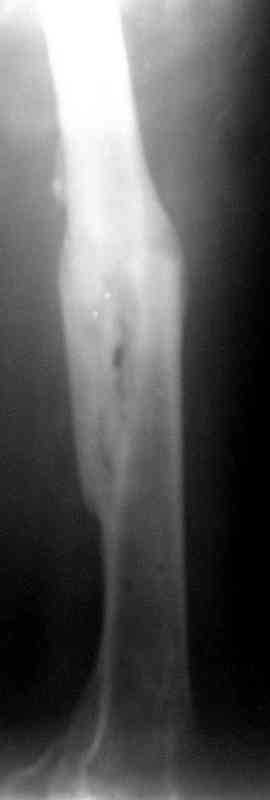

Уважаемые коллеги!На прилагаемых снимках - состояние после оперативного вмешательства (открытый перелом левого бедра в средней трети):

МОС, стержень нефиксированный. С момента операции прошло 8 месКак по Вашему мнению происходит консолидация? Допустимо ли смещение или необходима повторная операция по выравниванию конечности? Если да, какой метод рекомендуете (фиксированный стержень, пластина)?Буду благодарен за оперативный ответ.

При таком диаметре штифта не удивительно, что перелом не сросся (кстати, какой диаметр и что за модификация штифта?).

А чего интересного тут можно ожидать? Явно была открытая репозиция. Фиксация при таком переломе таким стержнем - это не очень состоятельный остеосинтез, неожиданностей не случилось.

Как по Вашему мнению происходит консолидация?

По-моему - замедлнно.

Допустимо ли смещение...

В этой проекции угловое смещение градусов 15-20 - многовато будет. Есть ли укорочение?